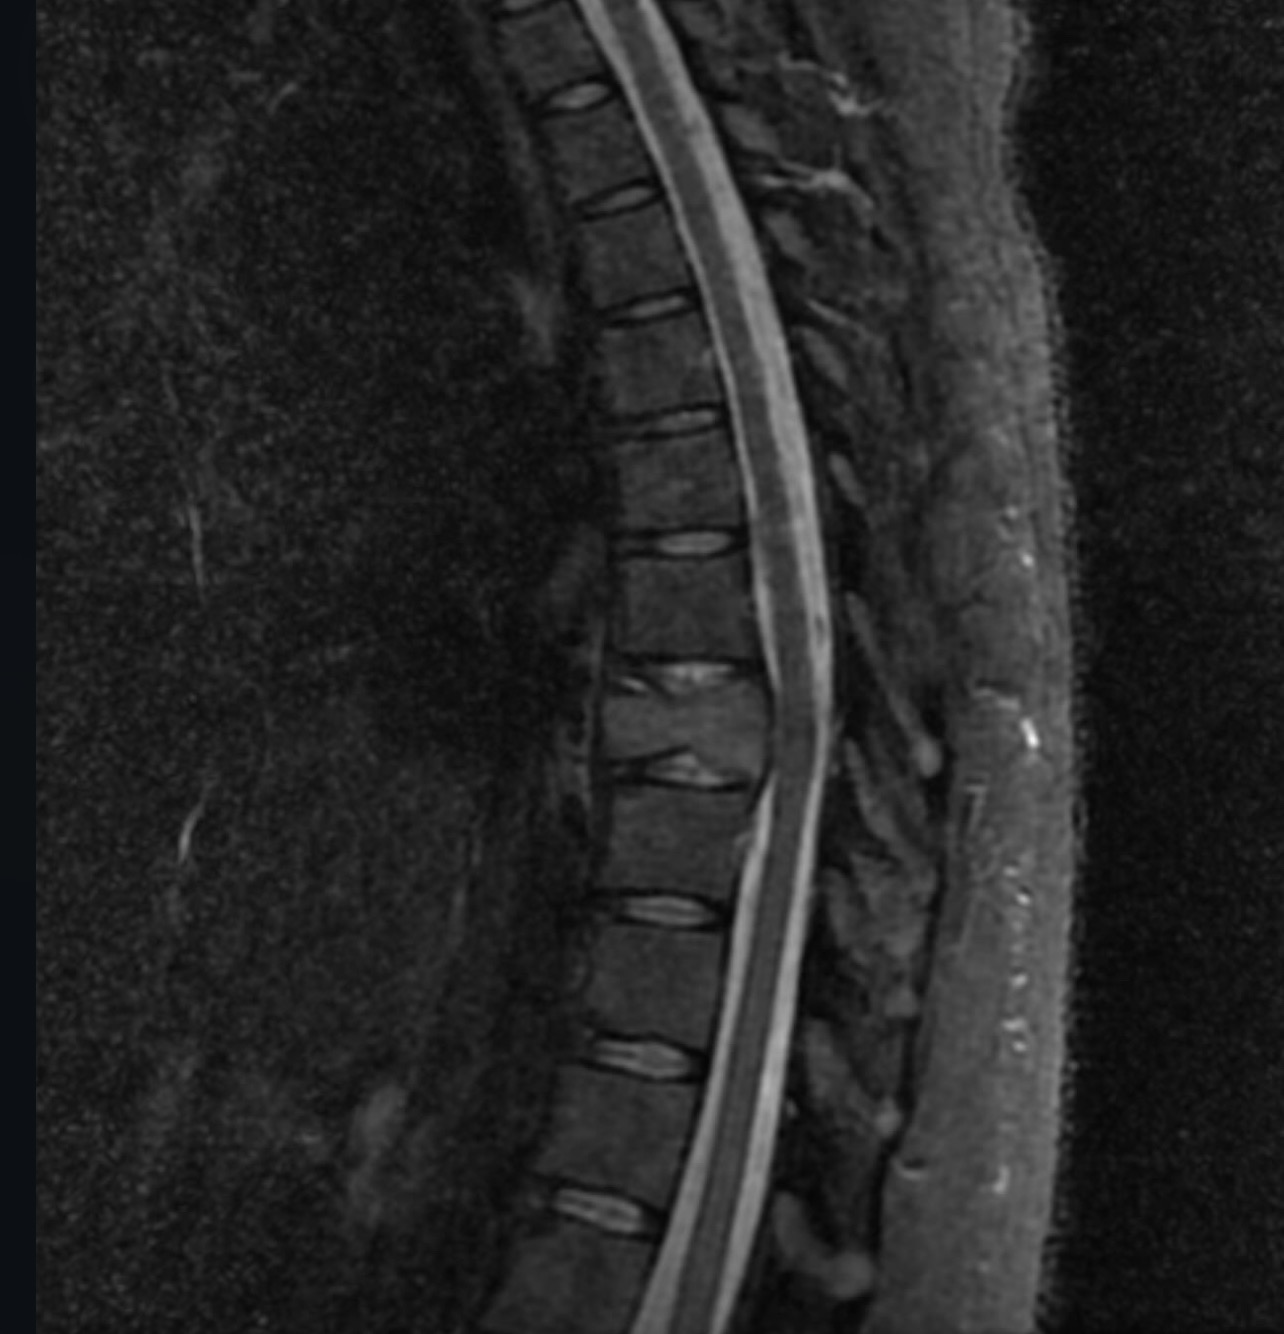

El pasado 31 de mayo de 2025, mientras viajaba en moto con mi padre, fuimos brutalmente atropellados. Yo llevaba casco, iba con precaución… pero la violencia del impacto me cambió la vida en segundos. Desde entonces, vivo con fracturas en mis costillas, una lesión lumbar y una fractura severa en la vértebra T8, que amenaza con dejarme sin movilidad si no recibo atención médica especializada de inmediato.

Diagnóstico actual: Fractura vertebral T8 postraumática con compromiso estructural grave + fracturas costales + protrusión discal lumbar